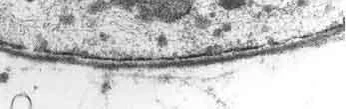

Морфологические структуры, ответственные за ГЭБ, были детально изучены в 1960-х годах методами электронной микроскопии[23][24].

Капиллярные сосуды выстланы эндотелиальными клетками. Эндотелий сосудов большинства тканей содержит открытые промежутки (фенестра́ции) диаметром около 50 нм и межклеточные щели от 100 до 1000 нм. Через эти промежутки вода и растворённые в ней вещества циркулируют между кровью и межклеточным пространством. Отличительной особенностью сосудов центральной нервной системы является отсутствие как фенестраций, так и межклеточных щелей между эндотелиальными клетками[30]. Таким образом, эндотелиальная выстилка капилляров мозга является сплошной[31].

Эндотелиальные клетки сосудов мозга плотно прилегают друг к другу. Между их стенками образуются так называемые плотные контакты, роль которых в обеспечении ГЭБ состоит в том, что они предотвращают проникновение в ткань мозга различных нежелательных веществ из кровеносного русла[45][46]. Плотные контакты между эндотелиальными клетками блокируют межклеточный (парацеллюля́рный) пассивный транспорт[47][48][49]. При этом блокируется парацеллюлярный транспорт веществ как из кровеносного русла в ткань мозга, так и в обратном направлении — из мозга в кровь[29].

Эндотелиальные клетки полностью покрывают подлежащий белковый слой, называемый база́льной мембраной[31]. Толщина базальной мембраны колеблется от 40 до 50 нм. Она различима только под электронным микроскопом. Состоит в основном из коллагена IV типа, гепаринсульфат-протеоглика́нов, ламини́нов, фибронекти́на и других белков внеклеточного матрикса. Со стороны мозга базальная мембрана ограничена плазматической мембраной пластинчатых окончаний отростков астроцитов[9][47].